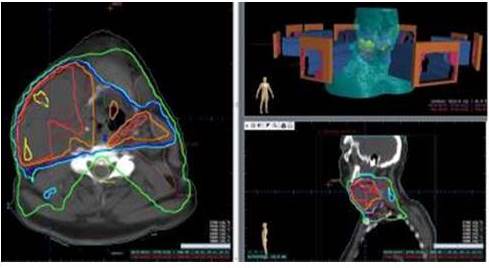

Utilizamos un sistema de planificación de tratamiento computarizado MIRS versión 6 (Figura 1). Se elaboró un primer plan, por 9 campos, 5 oblicuos, dos laterales, uno anterior y uno posterior, del cual se entregaron 4 320 cGy en 36 fracciones de 120 cGy por fracción (Figura 2).

Durante los controles semanales intra-tratamiento, se constata una modificación del volumen blanco, por lo cual se decide realizar otra tomografía de simulación para elaborar un nuevo plan de RT adaptativa (18).

El segundo plan, constituido también por 9 campos con una disposición similar a la primera, planificando 32 fracciones de 120 cGy (Figura 3).

Para el tratamiento utilizamos un acelerador lineal con energía de 6 MeV con colimador multiláminas. El mismo no presentó interrupciones, cumplió con los controles semanales con radioterapeuta de referencia, así como con los controles bisemanales con hemograma. No presentó complicaciones mayores.